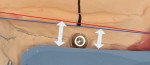

After extensive clinical and radiological examination, the treatment plan developed for the patient called for creation of a complete maxillary denture and a screw-retained permanent hybrid mandibular bridge. To retain the mandibular denture, four CAMLOG implants (CAMLOG, www.camlog.com) were placed in the mandible. Following the placement of the implants, impressions were taken and sent to the dental laboratory. From the impressions, master casts were created and mounted on an articulator (Candulor CA II, Candulor ). The condyle path inclination of the articulator was adjusted to 28º on the right and 30º on the left in neutral occlusion (Figure 1).

The mandibular restoration must be accessable between the implants for cleaning with interdental brushes. The ovate pontic on the soft tissue should not display any saddle-like constellations (ridge laps) and must be cleanable with dental floss. The denture would be mounted on an implant bar with passive bonding on the framework.